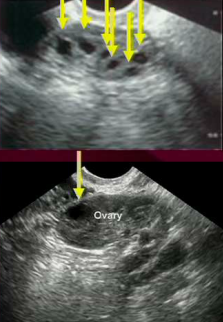

Hydrosalpinx

Obstruction of the fallopian tube that prevents fertilization, destroys the tube and fluid can reflux into uterus and kill the embryo.

What factors can be used to predict diminished ovarian reserve?

Age, FSH (more is produced because of low estrogen feedback w/diminished ovarian function), anti-mullerian hormone (healthy granulosa cells produce this) and astral follicle count on U/S (< 4 = poor fertility).